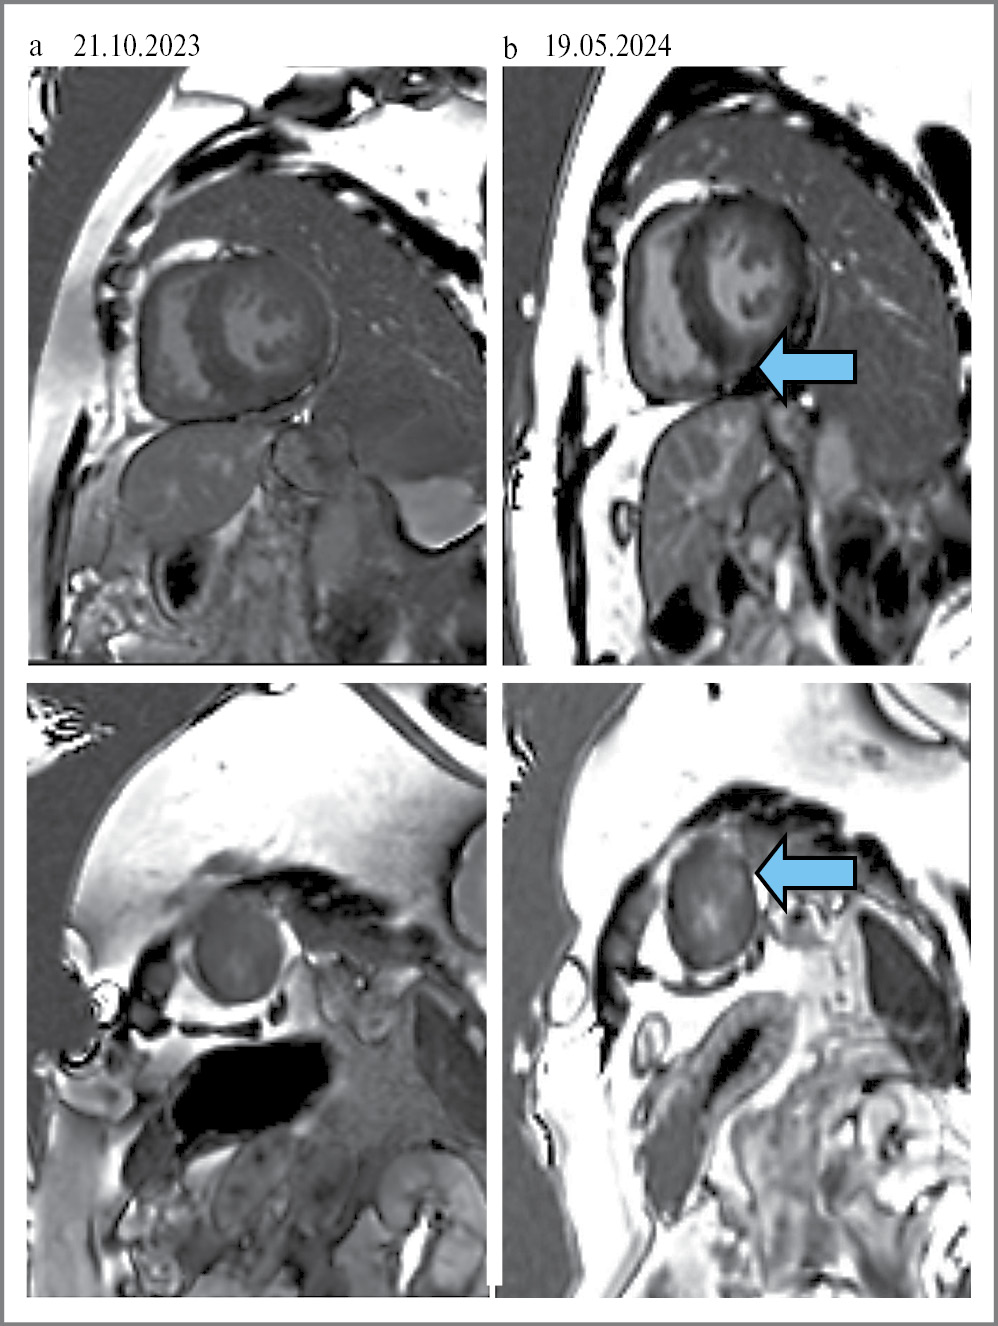

Выполнена коронароангиография от 15.11.2022: атеросклероз коронарных артерий без значимых стенозов. С 21.11.2022 в условиях кардиологического отделения №2 ГБУЗ ТО «ОКБ №1» инициирована ФЗТ. Все последующие инфузии ферментозаместительного препарата, вводимого через инфузомат и систему с фильтром, переносила удовлетворительно. Во время очередной госпитализации 13.10.2023 пациентка предъявила жалобы на прогрессирование одышки при физической активности, появление отеков лица в утренние часы. Холтеровское мониторирование электрокардиограммы (ЭКГ) от 16.10.2023: ритм синусовый 52–129–64 уд/мин, полиморфная желудочковая эктопическая активность в виде 2458 одиночных и 9 парных экстрасистол и неустойчивая желудочковая тахикардия с высокой частотой сердечных сокращений (2 эпизода) до 130 уд/мин и общей длительностью 6 с, 4 пробежки предсердной тахикардии, удлинение корригированного QT-интервала. МРТ сердца с внутривенным контрастированием от 21.10.2023: межжелудочковая перегородка (МЖП) – до 20 мм, боковая стенка – 27 мм. Толщина стенок правого желудочка (ПЖ) – до 9 мм. Поперечный размер ПЖ в диастолу – 79×32 мм. Продольный размер ПЖ – 63 мм. Фракция выброса (ФВ) – 64%, масса миокарда ЛЖ – 235 г. На постконтрастных изображениях участков замедленного вымывания контрастного вещества (КВ) не выявлено. Заключение: МР-картина симметричной гипертрофии миокарда ЛЖ; стеноз аортального клапана; средняя степень аортальной регургитации; эктазия ствола легочной артерии (ЛА), расширение ветвей ЛА; интрамиокардиального фиброза на момент исследования не получено. Пациентка консультирована сердечно-сосудистым хирургом, документы направлены в ФГБУ «НМИЦ им. акад. Е.Н. Мешалкина» для определения дальнейшей тактики ведения и лечения. Получен ответ 24.10.2023: показания к операции миоэктомии пути оттока ЛЖ сомнительны, продолжить специфическую терапию заболевания. Получены результаты из ФГБНУ «МГНЦ им. акад. Н.П. Бочкова» 26.10.2023: Lyso-Gb3 повышена – 5,04 нг/мл (норма – 0,05–3 нг/мл); 18.04.2024 впервые зафиксирован PQ/PR менее 120 мс (рис. 1). МРТ сердца с внутривенным контрастированием от 19.05.2024: МЖП – до 20 мм, боковая стенка – 10–12 мм. Конечно-диастолический размер ЛЖ – 45 мм, конечно-систолический размер ЛЖ – 26 мм, продольный размер ЛЖ – 97 мм. Толщина стенок ПЖ – до 4–5 мм, ФВ – 74%, масса миокарда ЛЖ – 287 г. На постконтрастных изображениях определяются интрамиокардиальные участки замедленного вымывания КВ по боковой стенке ЛЖ на уровне среднего и апикального сегмента, МЖП апикально соответствует зонам фиброзных изменений. Заключение: МР-картина асимметричной гипертрофии миокарда ЛЖ с признаками фиброзных изменений. Стеноз аортального клапана, аортальная регургитация 1-й степени. Эктазия ствола ЛА, расширение ветвей ЛА. В ФГБНУ «МГНЦ им. акад. Н.П. Бочкова» 30.07.2024 определена концентрация Lyso-Gb3 – 4,27 нг/мл (норма – 0,05–3 нг/мл). Динамика лабораторных исследований представлена в виде графиков (рис. 2, а, b). Данные эхокардиографии (ЭхоКГ) за 2 года наблюдения представлены в табл. 1.

В настоящее время для диагностики поражения сердца при БФ широко используется МРТ. ГЛЖ является наиболее распространенным структурным изменением, зарегистрированным при БФ. У пациентов преимущественно наблюдается концентрическая ГЛЖ с гипертрофией папиллярных мышц в начале, а асимметричная гипертрофия с грубо утолщенной перегородкой по сравнению с нижнебоковой стенкой развивается на поздних стадиях – заместительный фиброз вызывает истончение стенки последней. До 50% пациентов с БФ при МРТ будут иметь признаки контрастирования миокарда базального сегмента заднебоковой стенки ЛЖ в отсроченную фазу [5]. У нашей пациентки наблюдается замедленное вымывание контраста по боковой стенке ЛЖ на уровне среднего и апикального сегментов, МЖП апикально (рис. 4, 5, a, b). Также в случае нативного Т1-картирования при БФ отмечается значимое снижение глобального Т1-времени релаксации, что обусловлено накоплением гликосфинголипидов в кардиомиоцитах. При Т2-картировании повышение Т2-времени релаксации отмечается изолированно в заднебоковом сегменте ЛЖ, где чаще всего при БФ выявляется отсроченное накопление гадолинийсодержащего контрастного препарата. Повышение Т2 в данном сегменте объясняется очаговым отеком миокарда, а он, в свою очередь, связан с аномалиями на ЭКГ, которые могут провоцировать аритмии, включая измененный интервал PQ/PR, блокаду ножек пучка Гиса и удлинение интервала QTc. Данный отек и выброс высокочувствительного тропонина у пациентов с БФ связаны именно с локальным воспалением миокарда [6].

Рис. 5. МРТ сердца пациентки. Двухкамерное сердце по короткой оси: a – на постконтрастных изображениях отсутствуют очаги замедленного вымывания КВ; b – на постконтрастных изображениях в динамике определяются интрамиокардиальные очаги замедленного вымывания КВ (указан стрелкой).

Fig. 5. MRI of the patient's heart. Two-chambered heart along the short axis: a – post-contrast images show absence of delayed contrast washout foci; b – the dynamic post-contrast images show the appearance of an intramyocardial focus of delayed contrast agent washout (indicated by the arrow).